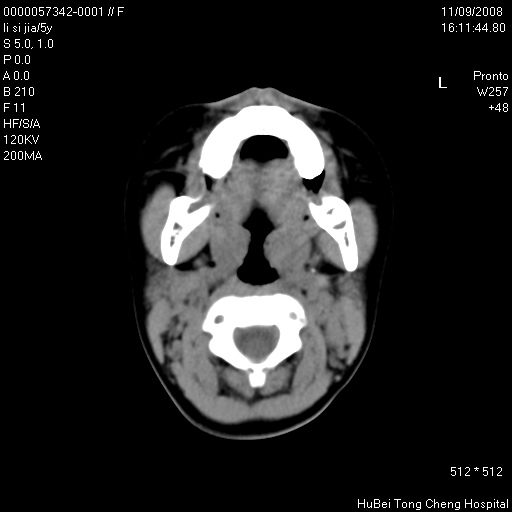

患儿 女,5岁。鼻塞、流涕2年余。

临床诊断:慢性副鼻窦炎?

副鼻窦ct轴位平扫(层厚、层距均为5mm),图像如下:

双侧上颌窦\\筛窦及蝶窦内均可见多量软组织密度影,结合病史支持考虑慢性全鼻窦炎

双侧上颌窦、筛窦及蝶窦内均可见粘膜增厚,结合病史支持考虑慢性全付鼻窦炎,腺样体肥大。